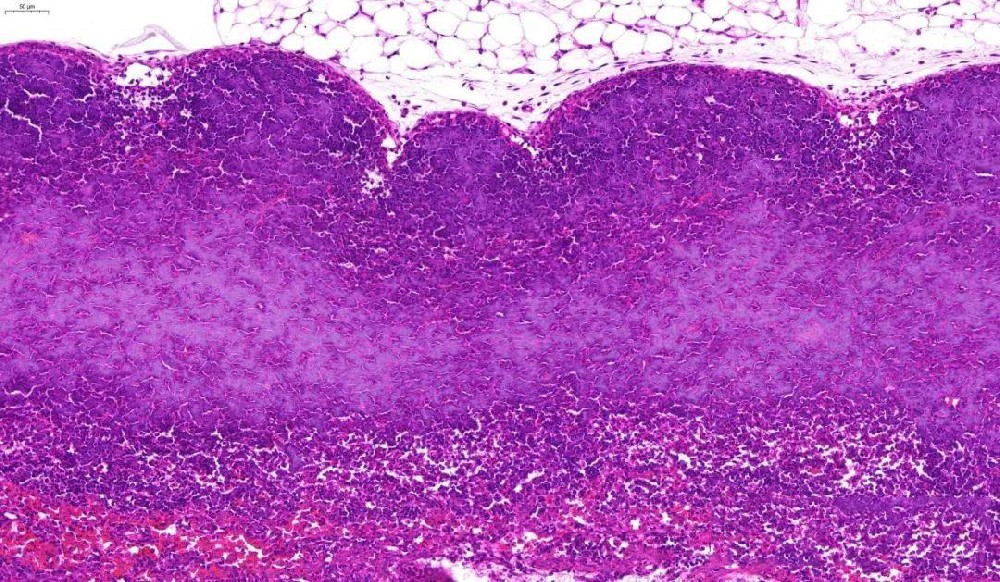

(一)實(shí)驗(yàn)?zāi)康耐ㄟ^蘇木素(堿性染料)和伊紅(酸性染料)對(duì)組織切片進(jìn)行染色,使細(xì)胞核、細(xì)胞質(zhì)呈現(xiàn)不同顏色,清晰顯示組織細(xì)胞的形態(tài)結(jié)構(gòu)、排列方式,為病理診斷提供基礎(chǔ)依據(jù)。(二)實(shí)驗(yàn)材料1. 樣本:已烤好的病理···